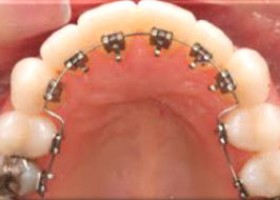

Lingual braces custom made fixed braces. In lingual braces the brackets are cemented onto the backside of the teeth making them invisible. Hence, Lingual braces are a cosmetic alternative to those who do not wish the braces to be visible. Lingual Braces are commonly used to fix Bad bite occurring as a result of misaligned teeth. Also used to correct Gaps, crowding, rotated teeth, hence improving the cosmetic appearance of the teeth.